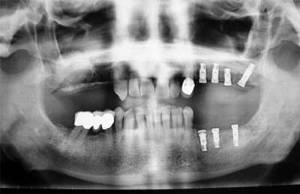

Implants dentals, inclusions dentàries (canins inclosos i queixals del seny), quists i tumoracions dels maxil·lars, boca, cap i coll, cirurgia dels teixits tous de la boca (làser de CO₂), patologia i cirurgia de les genives (periodòncia), càncer de boca, deformitats dentofacials, traumatismes de la boca i de la cara, patologia de les glàndules salivals.

Hi ha moltes tècniques i patologies que poden incloure’s en aquesta especialitat, però en destacarem algunes de les més importants: